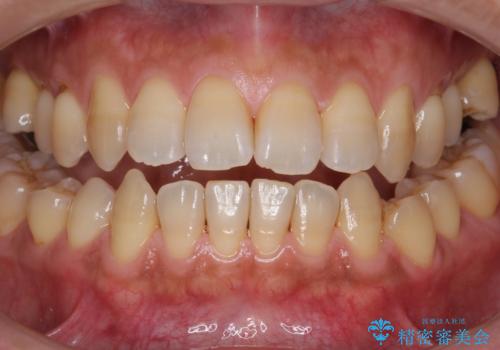

- 半年ぶりの来院で、全体的なチェックとクリーニング希望でした。PMTC(自費クリーニング)60分コースを行いました。

PMTCとは、プロフェッショナル(歯科衛生士)メカニカル(機械的)トゥース(歯)クリーニング(清掃)の略です。歯科医院にて、いろいろな機械・材料を使用し汚れを落とします。

磨き残しや、細菌は歯の表面がザラザラしている部分につきやすいです。そのためPMTCを定期的に繰り返すことで、歯の表面がツルツルの状態である期間が長くなるため、虫歯や歯周病予防につながります。